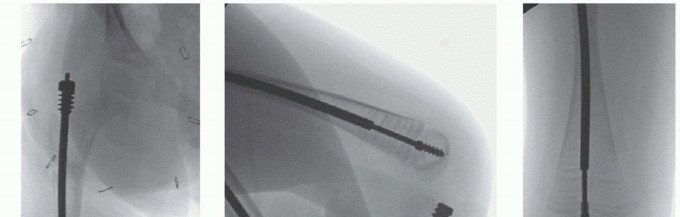

## The canal is reamed over the guidewire down to the distal femoral metaphysis, approximately 1 cm proximal to the physis in the center-center position on both AP and lateral radiographs (TECH FIG 2A-C).

## The nail and driver are passed to the center-center position in the distal metaphysis (TECH FIG 2C).

TECH FIG 2 • A. The guidewire and reamer must be extended to the distal metaphysis in the central position on both the AP and lateral planes. The reamer can easily bind on the guidewire and be pushed distally. B,C. The male nail is then inserted to the center-center position at the distal metaphysis. At this point, valgus, varus, and distal flexion can be corrected. D. The male nail driver must be unlocked prior to removing the new locking male driver, if the male nail is not precut. The long probe or another male nail must be used to prevent backing out of the male nail, whether precut or full length. E. The male nail guides must be engaged with the male driver.

## To measure the length of the female rod intraoperatively, it is placed with the threaded portion just at the top of the ossified greater trochanter with C-arm verification using a metal marking device distally approximately 1 cm above the physis (TECH FIG 3A).

## The cannulated portion must be checked to ensure that no metal will impinge on the male nail to prevent it from lengthening and that any metal shards are rinsed off (TECH FIG 3B,C).

## A circular saw and rod holder are also available from the manufacturer to cut the female rod (TECH FIG

3D).

## The female nail is then screwed into the greater trochanter with the T-handle screwdriver until just a few threads are engaging the bony portion of the proximal femur just distal to the greater trochanter (TECH FIG 3E).

## The female nail is checked distally to be sure there is some space between its distal end and the guide wings of the male nail to ensure that the male nail is not driven distally into the joint either acutely or with impaction of the osteotomy with weight bearing (TECH FIG 3F,G).

TECH FIG 3 • A. Measuring the female nail length intraoperative with fluoroscopy. B,C. Cutting the rod with diamond burr. D. Manufacturer's female nail holder with cutting wheel and burr to smooth rough internal edges after cutting. (continued)

## TECH FIG 3 • (continued) E. The female threads are shown engaging the bone just distal to the greater trochanter to mitigate overgrowth of the trochanter apophysis but avoid proximal migration of the female nail. F,G. Distal placement of the male nail driver and nail in the center-center position is mandatory. The threads engage the epiphysis of the distal femur with the rounded, smooth portion traversing the physis.

Ideally, the distal end of the female nail is as close as possible to the guide wings of the male nail for strength and growth but leave room for compression at the osteotomy. H. The male nail is cut in situ with the male nail cutter. (D: Courtesy of Pega Medical, Inc., Montreal, Canada.)